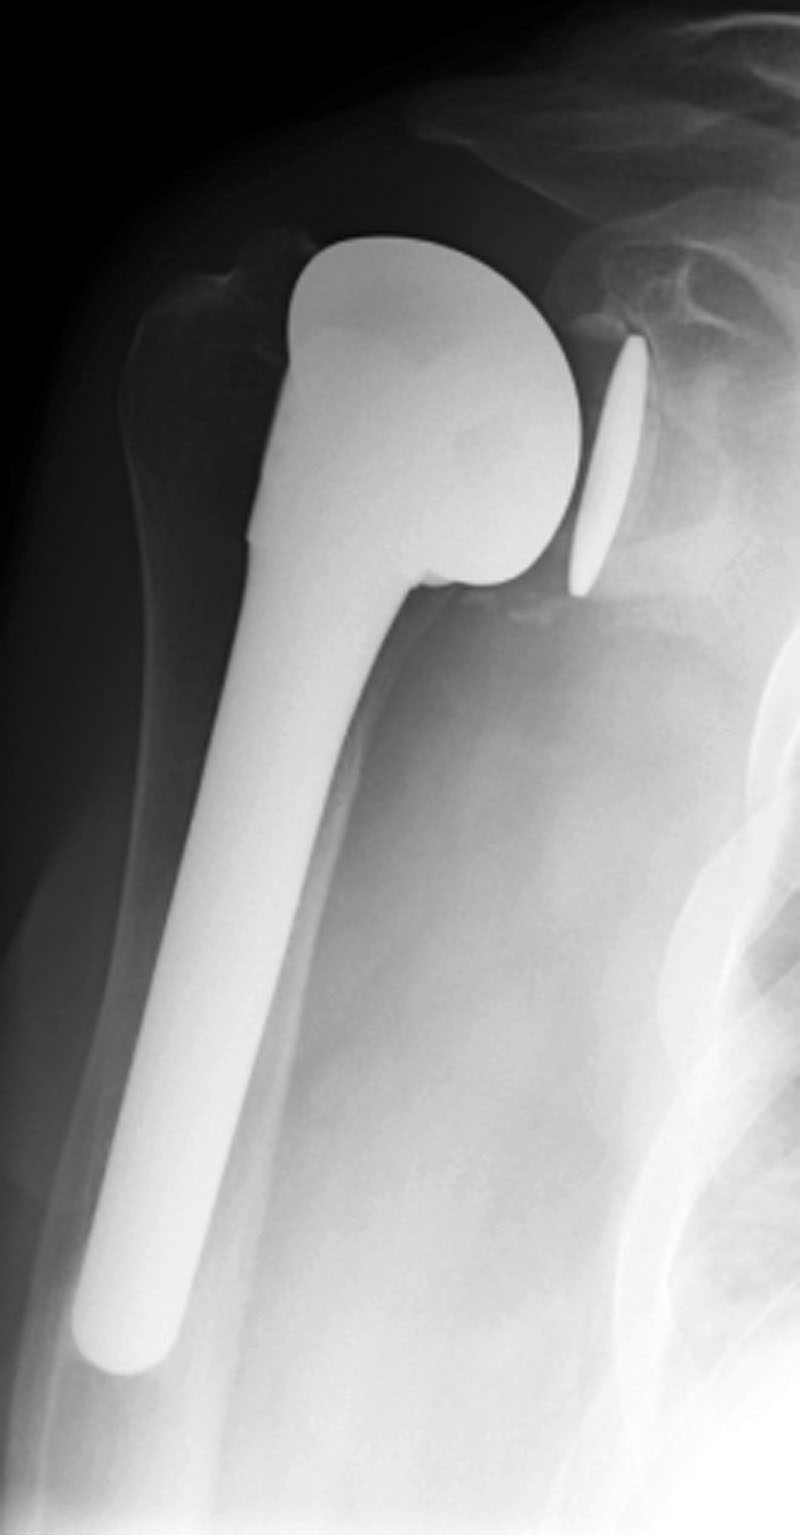

| Right shoulder hemiarthroplasty |